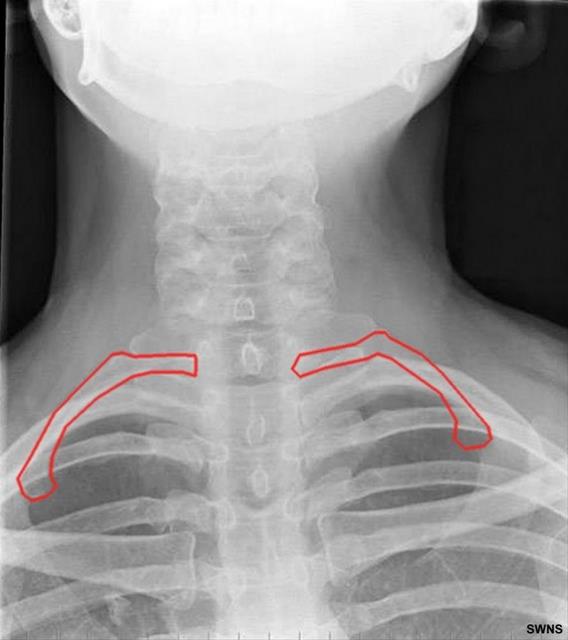

7. Her 20 kişiden birinin ve çoğunlukla da erkeklerin kaburga sayısı 1 fazla.

Her 20 kişiden birinin ve çoğunlukla da erkeklerin kaburga sayısı 1 fazla.